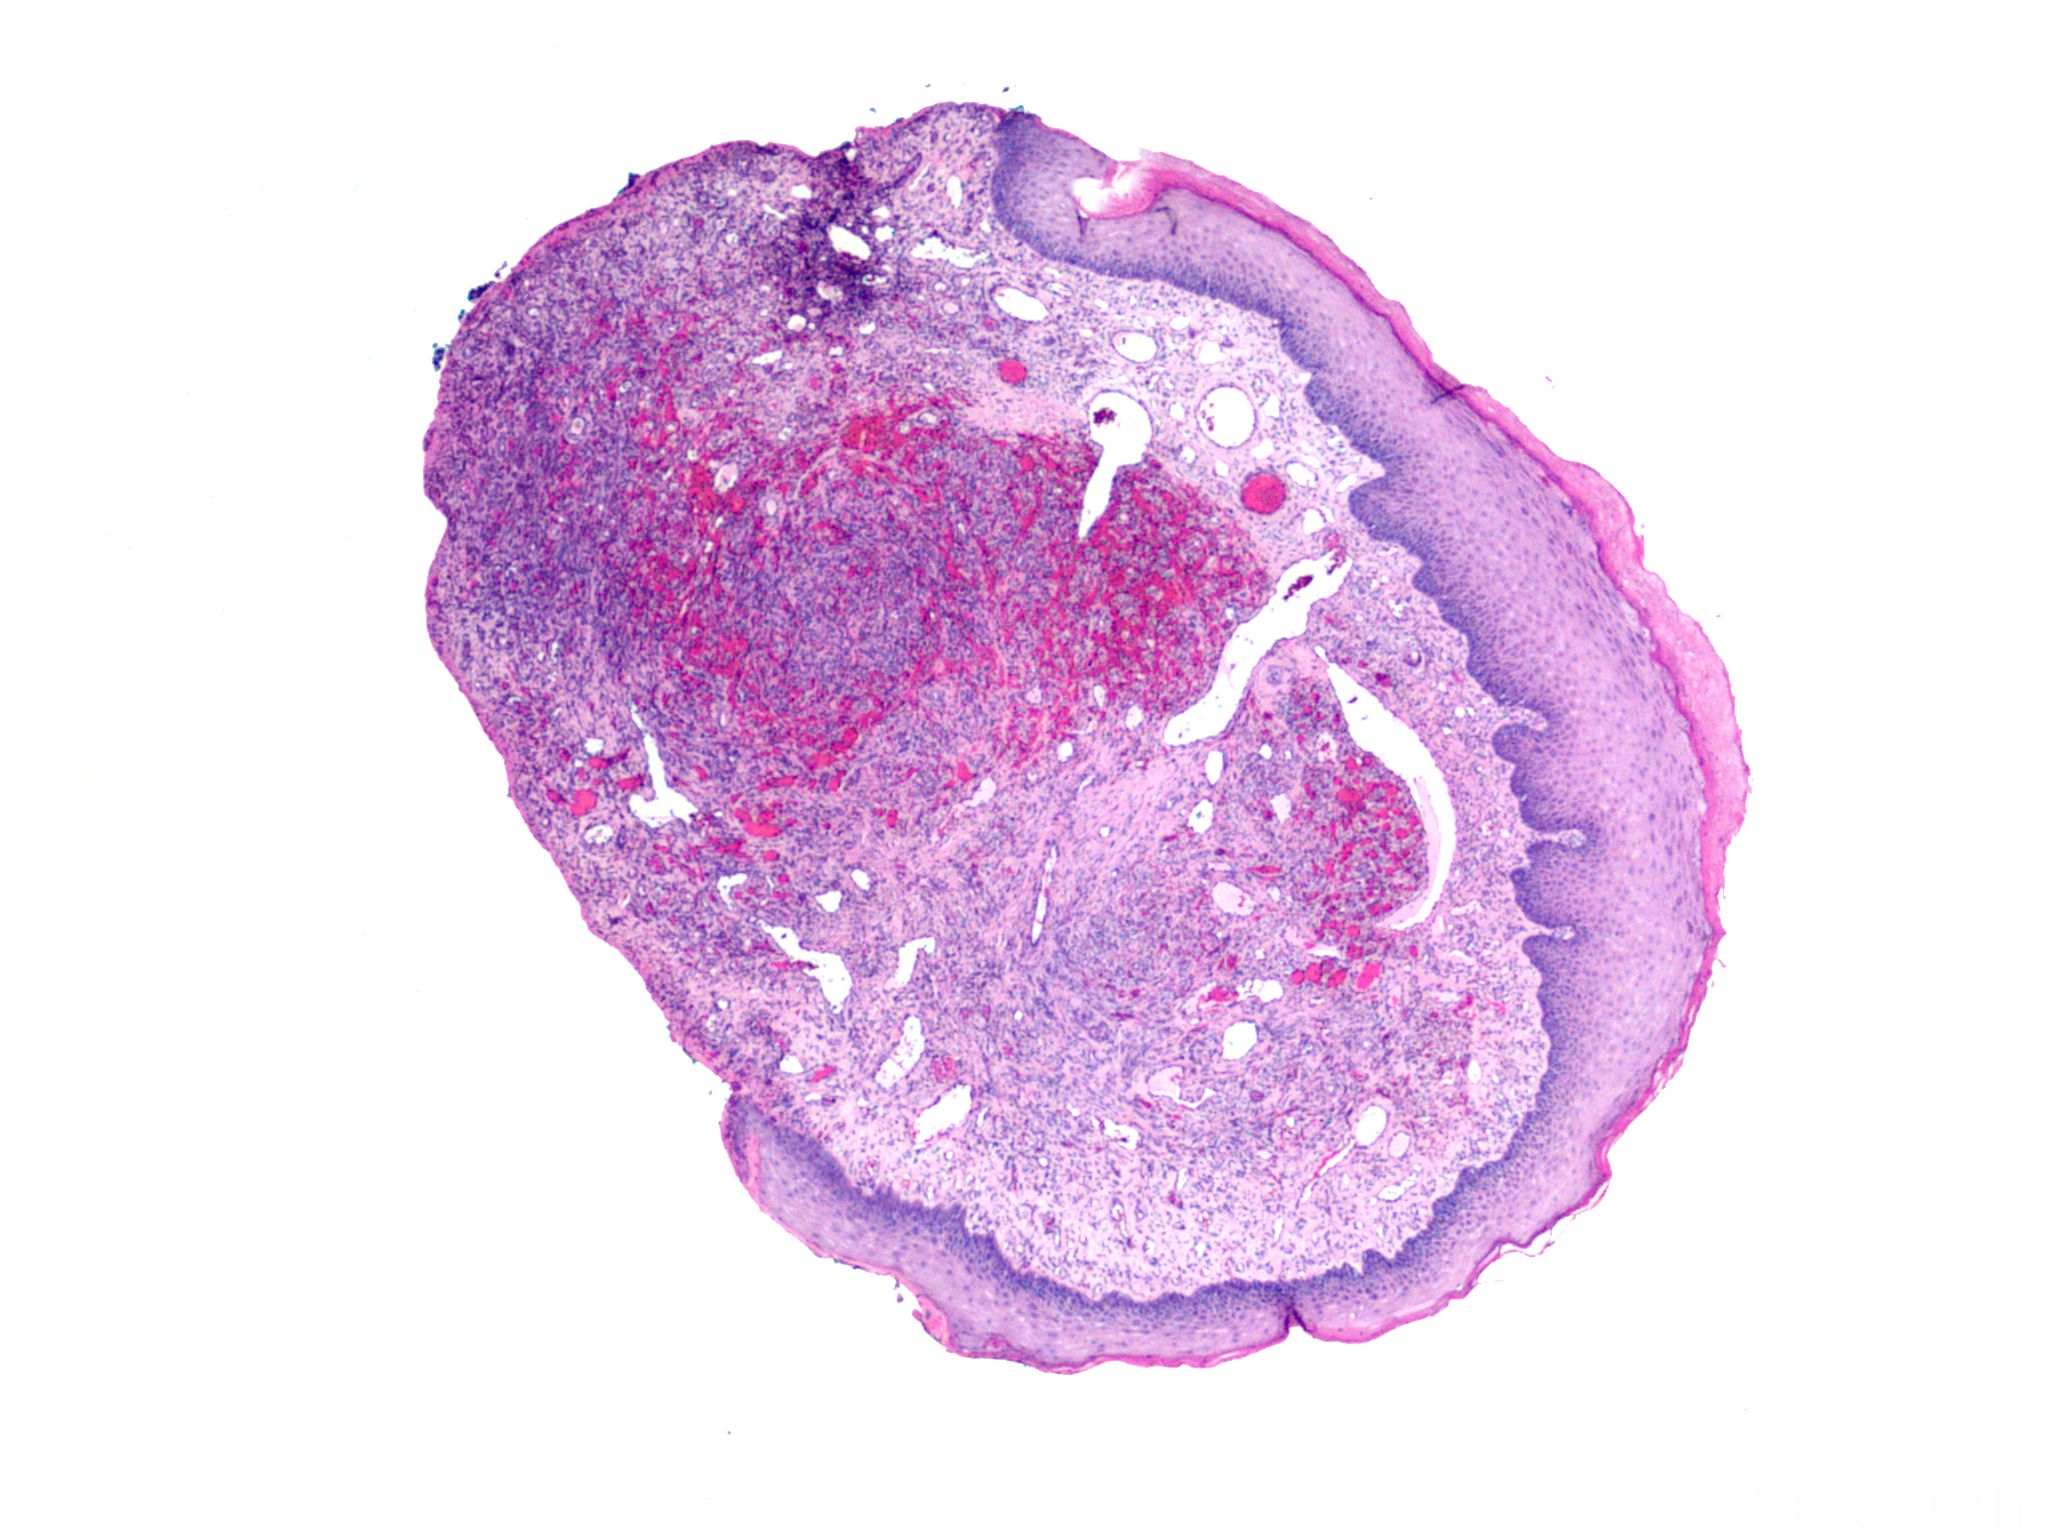

典型的卡波西肉瘤细胞无明显的异型性,核分裂像也不多见,但少数病例中瘤细胞分化较差,异型性明显,可见较多的核分裂像。依据病变进展分为四期:

IV 期为结节期:结节期的病变边界清楚,主要由网状或裂隙状的毛细血管及其周围纵横交错的嗜酸性梭形细胞组成,梭形细胞有一定异型性,核分裂偶见;梭形细胞和血管之间为含有红细胞的裂隙,横切面呈筛孔状或蜂窝状,在梭形细胞内或细胞外可见抗淀粉酶消化 PAS 阳性的嗜伊红色透明小体,结节的边缘常见炎症细胞浸润、含铁血黄素沉着和扩张的血管。 典型的卡波西肉瘤细胞无明显的异型性,核分裂像也不多见,但少数病例中瘤细胞分化较差,异型性明显,可见较多的核分裂像。